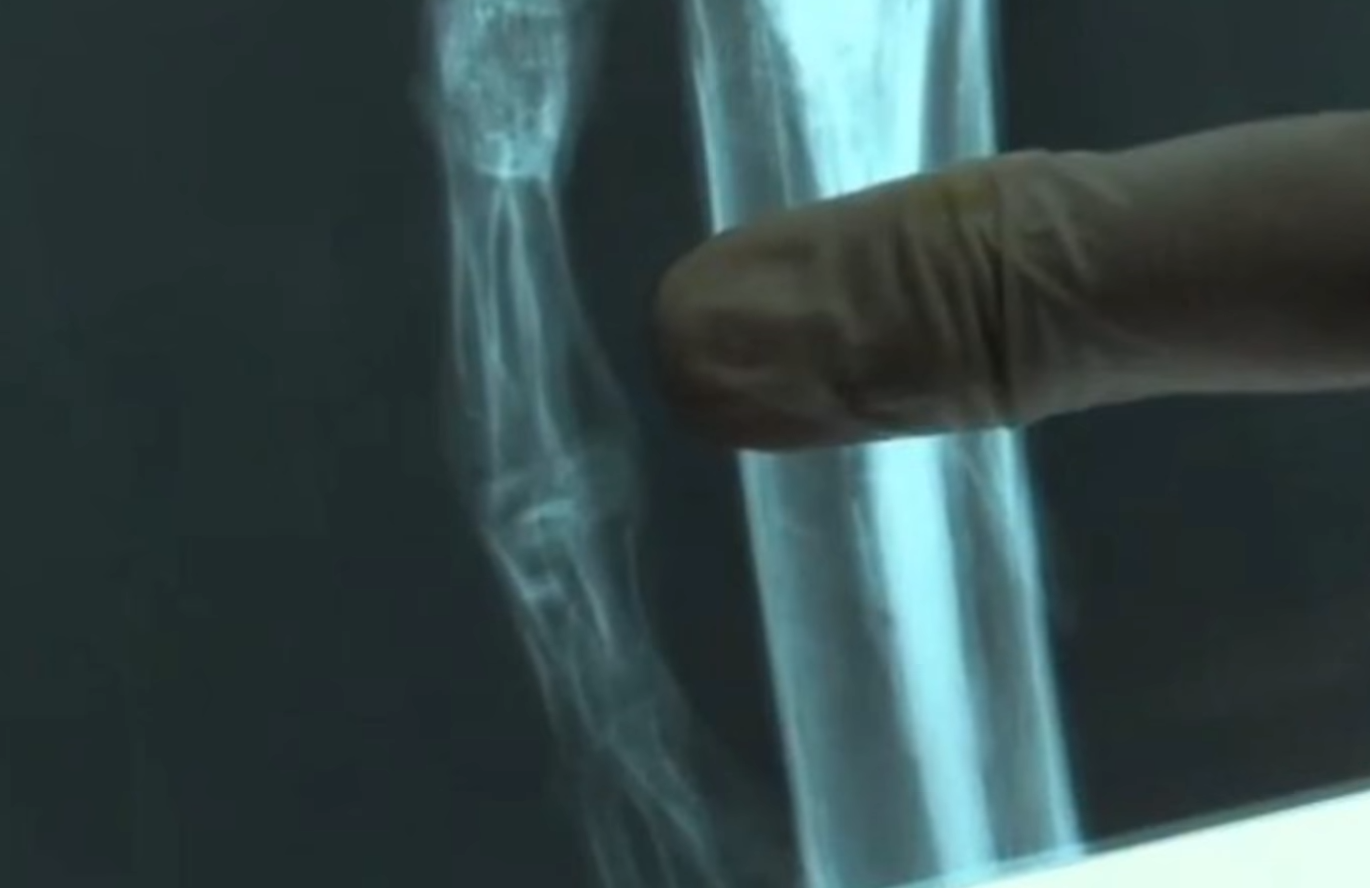

Крім цього, вона має лише десять пар ребер (на відміну від дванадцяти звичайних для людини), а її кістки - занадто "зрілі" (на це вказує їхня щільність і форма).

На детальне вивчення Ати в каліфорнійському Стенфордському університеті пішло близько пів року. Аналіз ДНК, узятий з кісткового мозку ребер, показав, що мумія являє собою рідкісну мутацію людини жіночої статі, або ж невідому раніше аномалію розвитку скелета.

На думку експертів, незвичайний зовнішній вигляд обумовлений негативними мутаціями у понад 60 різних генах.

Водночас низка інших вчених з університетів Нової Зеландії, США, Швеції та Чилі поставили під сумнів висновки дослідників зі Стенфордського університету, оскільки не виявили в мумії ніяких ознак скелетних аномалій плода.